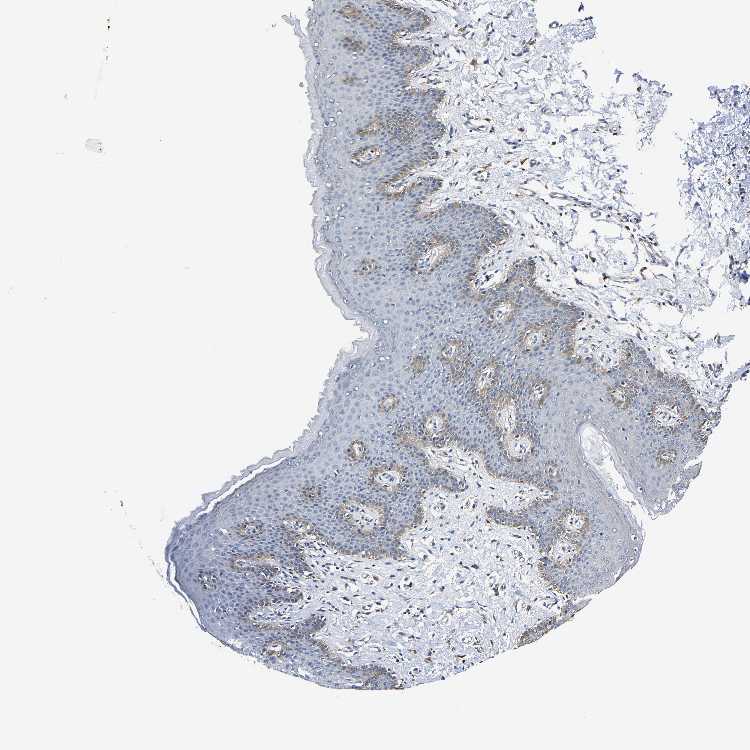

SKIN 2 - Antibody stainingi

Antibody staining in the annotated cell types in the current human tissue is reported as not detected, low, medium, or high, based on conventional immunohistochemistry profiling in selected tissues. This score is based on the combination of the staining intensity and fraction of stained cells.

Each image is clickable and will lead to virtual microscopy that enables deeper exploration of all samples and also displays staining intensity scores, fraction scores and subcellular localization as well as patient and tissue information for each sample.

Antibody HPA019805Antibody HPA020599Antibody CAB004605

Epidermal cells MediumNot detectedMedium